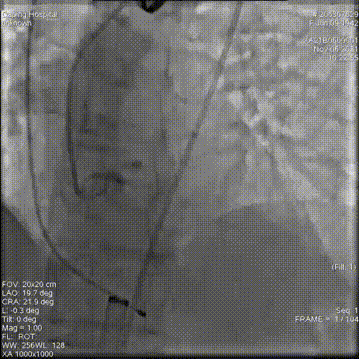

主动脉根部造影

18mm球囊预扩

第一次释放,位置过高回收定位

第二次释放,位置过低再回收释放

第三次瓣膜释放定位

23mm瓣膜释放中

20mm球囊后扩前造影

术后造影